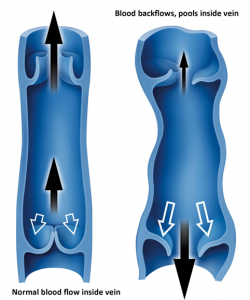

نارسایی دریچه ای در وریدهای عمقی و یا وریدهای پرفوریتور (ناهنجاری های مادرزادی، تغییرات سنی)

ترومبوز وریدهای عمقی و انسداد جریان خون اختلال پمپ عضلانی بدلیل کاهش حرکت عضو یا مفصل مچ پا در اثر فلج